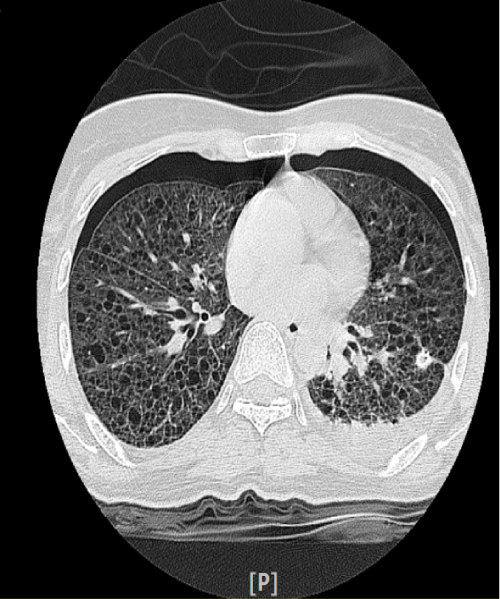

Figure 2: HRCT Thorax showing bilateral pneumothoraces with multiple diffuse thin wall cysts of various sizes.